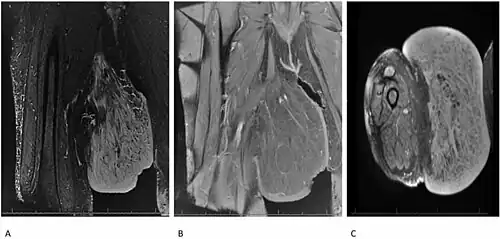

Diagnosis of Dercum's disease is done through a physical examination. In order to properly diagnose the patient, the doctor must first exclude all other possible differential diagnoses. The basic criteria for Dercum's disease are patients with chronic pain in the adipose tissue (body fat) and patients who are also obese. Although rare, the diagnosis may not include obesity.[5] Dercum's disease can also be inherited and a family medical history may aid in the diagnosis of this disease.[5] There are no specific laboratory test for this disease. Ultrasound and magnetic resonance imaging can play a role in diagnosis.[10]

- ↑ Tins, B.J.; Matthews, C.; Haddaway, M.; Cassar-Pullicino, V.N.; Lalam, R.; Singh, J.; Tyrrell, P.N.M. (27 June 2013). "Adiposis dolorosa (Dercum's disease): MRI and ultrasound appearances". Clinical Radiology. Elsevier. 68 (10): 1047–53. doi:10.1016/j.crad.2013.05.004. PMID 23809264.